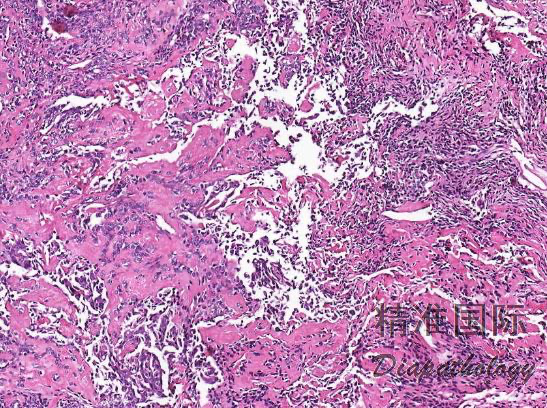

根据组织形态及分化程度不同,可分为双向型滑膜肉瘤、单向梭形细胞型滑膜肉瘤、单相上皮性滑膜肉瘤、低分化型滑膜肉瘤、高分化型滑膜肉瘤、硬化性滑膜肉瘤: 1)双相型滑膜肉瘤:由比例不等的上皮样瘤细胞和梭形细胞组成,两种细胞之间有移行; 2)上皮样细胞: a)呈立方形或柱状,胞质丰富、嗜酸性或清亮,核圆形、卵圆形,呈空泡状; b)常形成腺样结构,腺腔内可见嗜伊红色的分泌物; c)还可排列成小管状、条索状或实性团块状、甚至腺泡状或乳头状,乳头轴心为梭形瘤细胞,而非纤维结缔组织; d)上皮样细胞巢周与梭形细胞之间缺乏典型的基膜; 3)梭形细胞: a)形态较一致,梭形或短梭形,核梭形或卵圆形,深染、核仁不明显,胞质少而不清晰,瘤细胞核质比大,以致核呈重叠状; b)细胞多呈实性片状或束状排列,也可呈栅栏状或鱼骨样排列,类似纤维肉瘤或恶性周围神经鞘膜瘤; c)梭形细胞间可含有多少不等的胶原纤维,呈粗细不等的带状或绳索样;间质也可出现局灶性黏液变性;

d)瘤细胞间常有肥大细胞浸润,甲苯胺蓝、Gimesa 染色或 CD117 标志物可清晰显示,对滑膜肉瘤的诊断有提示意义。

- 单相梭形细胞型滑膜肉瘤: 1)瘤组织主要由短条束状或漩涡状排列的梭形瘤细胞构成; 2)分化差者可呈长条束状、鱼骨样或人字形排列; 3)瘤细胞间常有肥大细胞浸润,甲苯胺蓝、Gimesa 染色或 CD117 标志物可清晰显示,对滑膜肉瘤的诊断有提示意义; 4)部分病例可有“鹿角样”血管; 5)梭形细胞型瘤细胞易发生透明变性,黏液变性,局灶性钙化等;

6)此型肿瘤恶性度高,易转移,5 年生存率低,预后差。